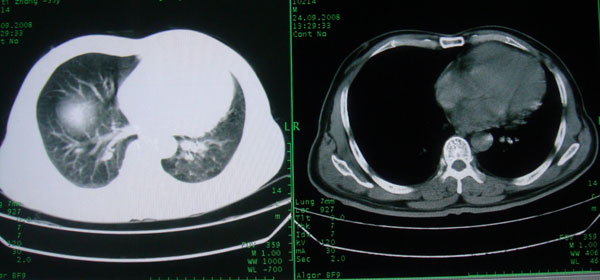

患者男性58岁因二周前起咳嗽,今天胸片示左上肺占位性病变行ct检查,无发热,无咯血痰.

左肺上叶病灶,实变但见含气支气管、空洞但未见壁内结节及积液;

考虑:①感染性病变(包括特殊感染型肺tb)

②肿瘤性病变(考虑患者年龄比较大的关系/所以不排除)

初学者。。。左肺空洞性病变,并可见阻塞性肺不张改变,鉴于患者为老年男性,且临床症状仅有咳嗽,全身中毒症状不明显,所以我首先考虑为左肺癌性空洞并左侧肺门淋巴结转移伴左肺阻塞性肺不张。结核性空洞放于第二位考虑,可以进行相关实验室检查。希望能有病理结果,谢谢!!!!!

抗炎治疗半月观察病灶大小的变化,如变化不明显,那就不除外肺泡癌的可能.

建议抗炎治疗两周后复查除外肺癌。

左肺上叶实变影,内见支气管充气征及空洞影,病人年龄较大,无发热及结核中毒症状,心影左移,未见纵隔淋巴结肿大;不知实验室检查结果如何?有否嗜酸细胞增多,有没有进行治疗?就目前资料首先考虑1.感染性病变,2.慢性嗜酸性肺炎?可结合实验室检查并短期治疗复查,肺癌不能排除。